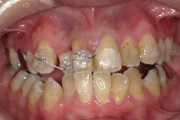

全体矯正症例

16才 女性

顎の成長が終了してから抜歯を行い、スペースを確保してそこにゆっくりと歯を移動させていきます。

歯並びも咬み合わせも整い、無事に矯正装置を外すことができました。

矯正前

矯正中

矯正後